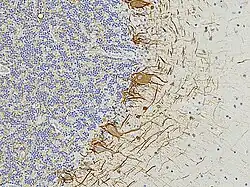

EnCor has always collaborated with basic scientists and clinicians to produce articles in peer-reviewed scientific publications focused on the examination of various plasma, serum and CSF biomarkers of nervous system damage and degeneration. One of these is the phosphorylated, axonal form of the major neurofilament protein heavy chain protein which has the HGNC name NEFH,[3][4][5][6] though is usually referred to as pNF-H in the scientific literature. Two further studies describe novel EnCor assays for UCHL1[7] and alpha-synuclein,[8] two major brain proteins implicated in the development of Parkinson's and other neurological diseases. In 2022 EnCor, in collaboration with researchers at the University of Florida described a novel class of antibodies to neurofilament light chain with the HGNC name NEFL, although the protein is usually referred to as NF-L. Surprisingly, one class of these antibodies bind epitopes hidden in healthy neurons and their processes but which are revealed on degeneration. Another class of antibody to neurofilament NF-L was shown to bind only neurofilaments in healthy neurons and their processes but failed to recognize degenerating and degenerated neurons and processes.[9] The antibodies degeneration specific antibodies have been dubbed "DegenoTag" reagents and should have wide utility for researchers on neurodegeneration. By 2022, the EnCor product line had increased to over 250 items, the antibodies mostly being used for research purposes, with a particular focus on immunocytochemistry and western blotting, though many are also utilized for immunocytochemistry, immunoprecipitation and ELISA. Some have become useful for diagnostic histopathology and for monitoring the levels of protein biomarkers, of research and potential clinical utility. EnCor supplies reagents to research labs and other reagent companies such as Abcam, BioLegend, Thermo Fisher Scientific, EMD Millipore, and Bio-Techne. EnCor is well known for the quality of its cell, tissue and western blotting images, many of which have been made available on Wikipedia Commons and widely used in books, articles, posters, for teaching, advertising and many other purposes, see [1].